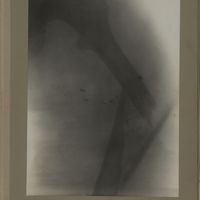

0138 - Page 26 - [Radiographie du fémur]0138 - Page 26 - [Radiographie du fémur]

0165 - Page 53 - [Radiographie du fémur]0165 - Page 53 - [Radiographie du fémur]

0168 - Page 56 - [Radiographie du fémur]0168 - Page 56 - [Radiographie du fémur]